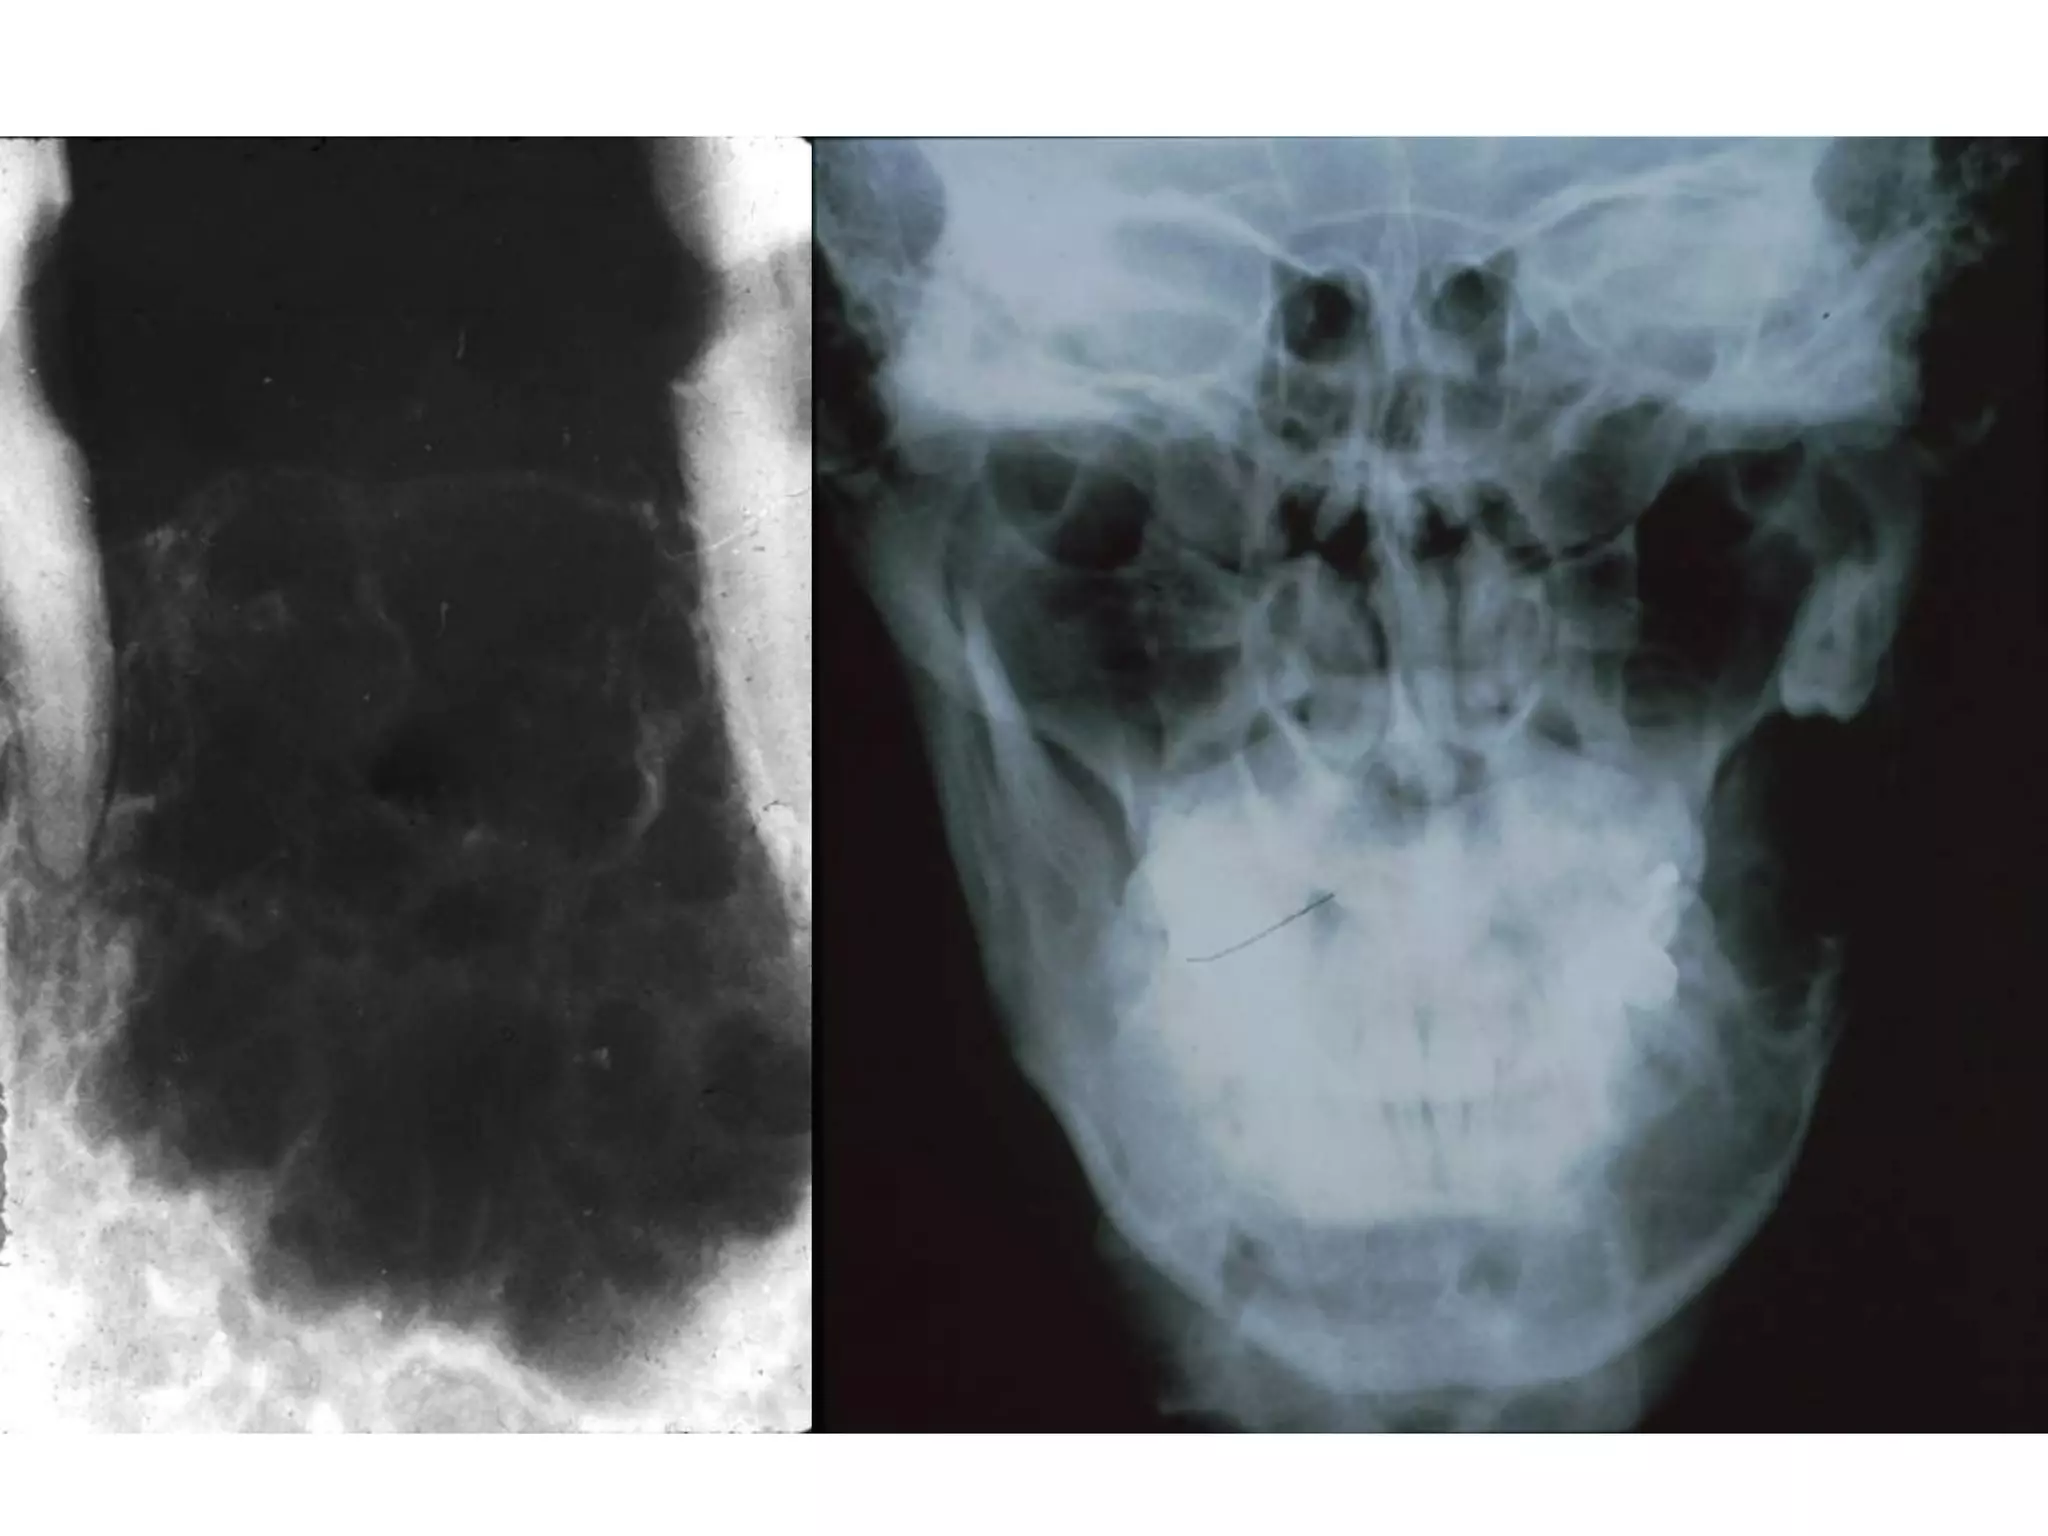

X quang: toån thöông thaáu quang thöôøng coù ranh giôùi roõ;

coù theå moät hoác hay nhieàu hoác (boït xaø phoøng, toå ong);

thænh thoaûng u coù ranh giôùi khoâng roõ, bôø nham nhôû.

X quang: thaáu quang quanh thaân raêng ngaàm (ña soá laø

RCL3 döôùi).

X quang:

 Ameloblastoma aùc tính: töông töï u men ñaëc

ñieån hình.

 Ameloblastic carcinoma thöôøng xaâm laán

nhieàu hôn, toån thöông thaáu quang ranh giôùi

khoâng roõ, phaù huûy voû xöông.